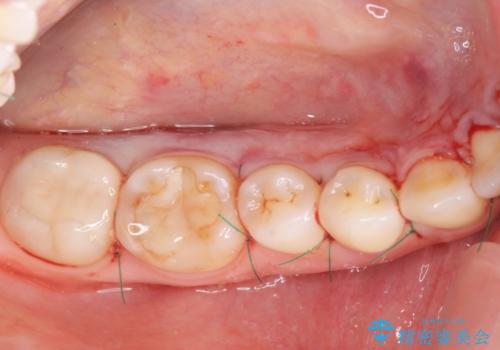

- 徐々に大きくなってきた骨隆起の除去を希望され来院されました。

下顎隆起を切除することで舌を収めるスペースを確保し発音のしやすさの向上を図ります。

手術は約1時間弱で終了し、術後もほとんど腫れは出ません。